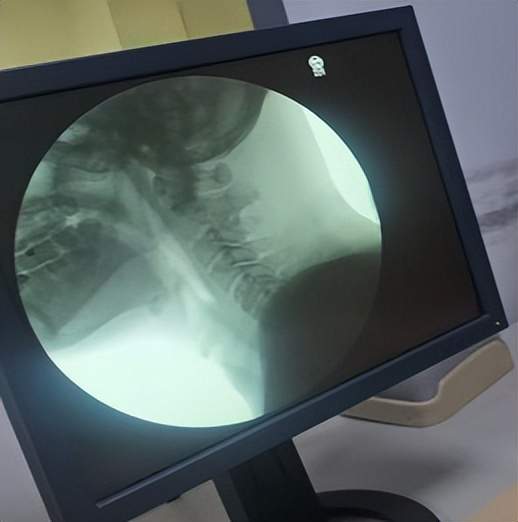

吞咽造影检查

为此,吞咽言语治疗科团队为徐大爷进行了吞咽造影检查。这项检查清晰地揭示了问题的关键所在:患者同时存在口腔期与咽期双重吞咽障碍——口腔肌肉力量不足、食团形成困难,咽期反射延迟、肌群运动不协调。这正是饮水呛咳、进食困难的核心原因。